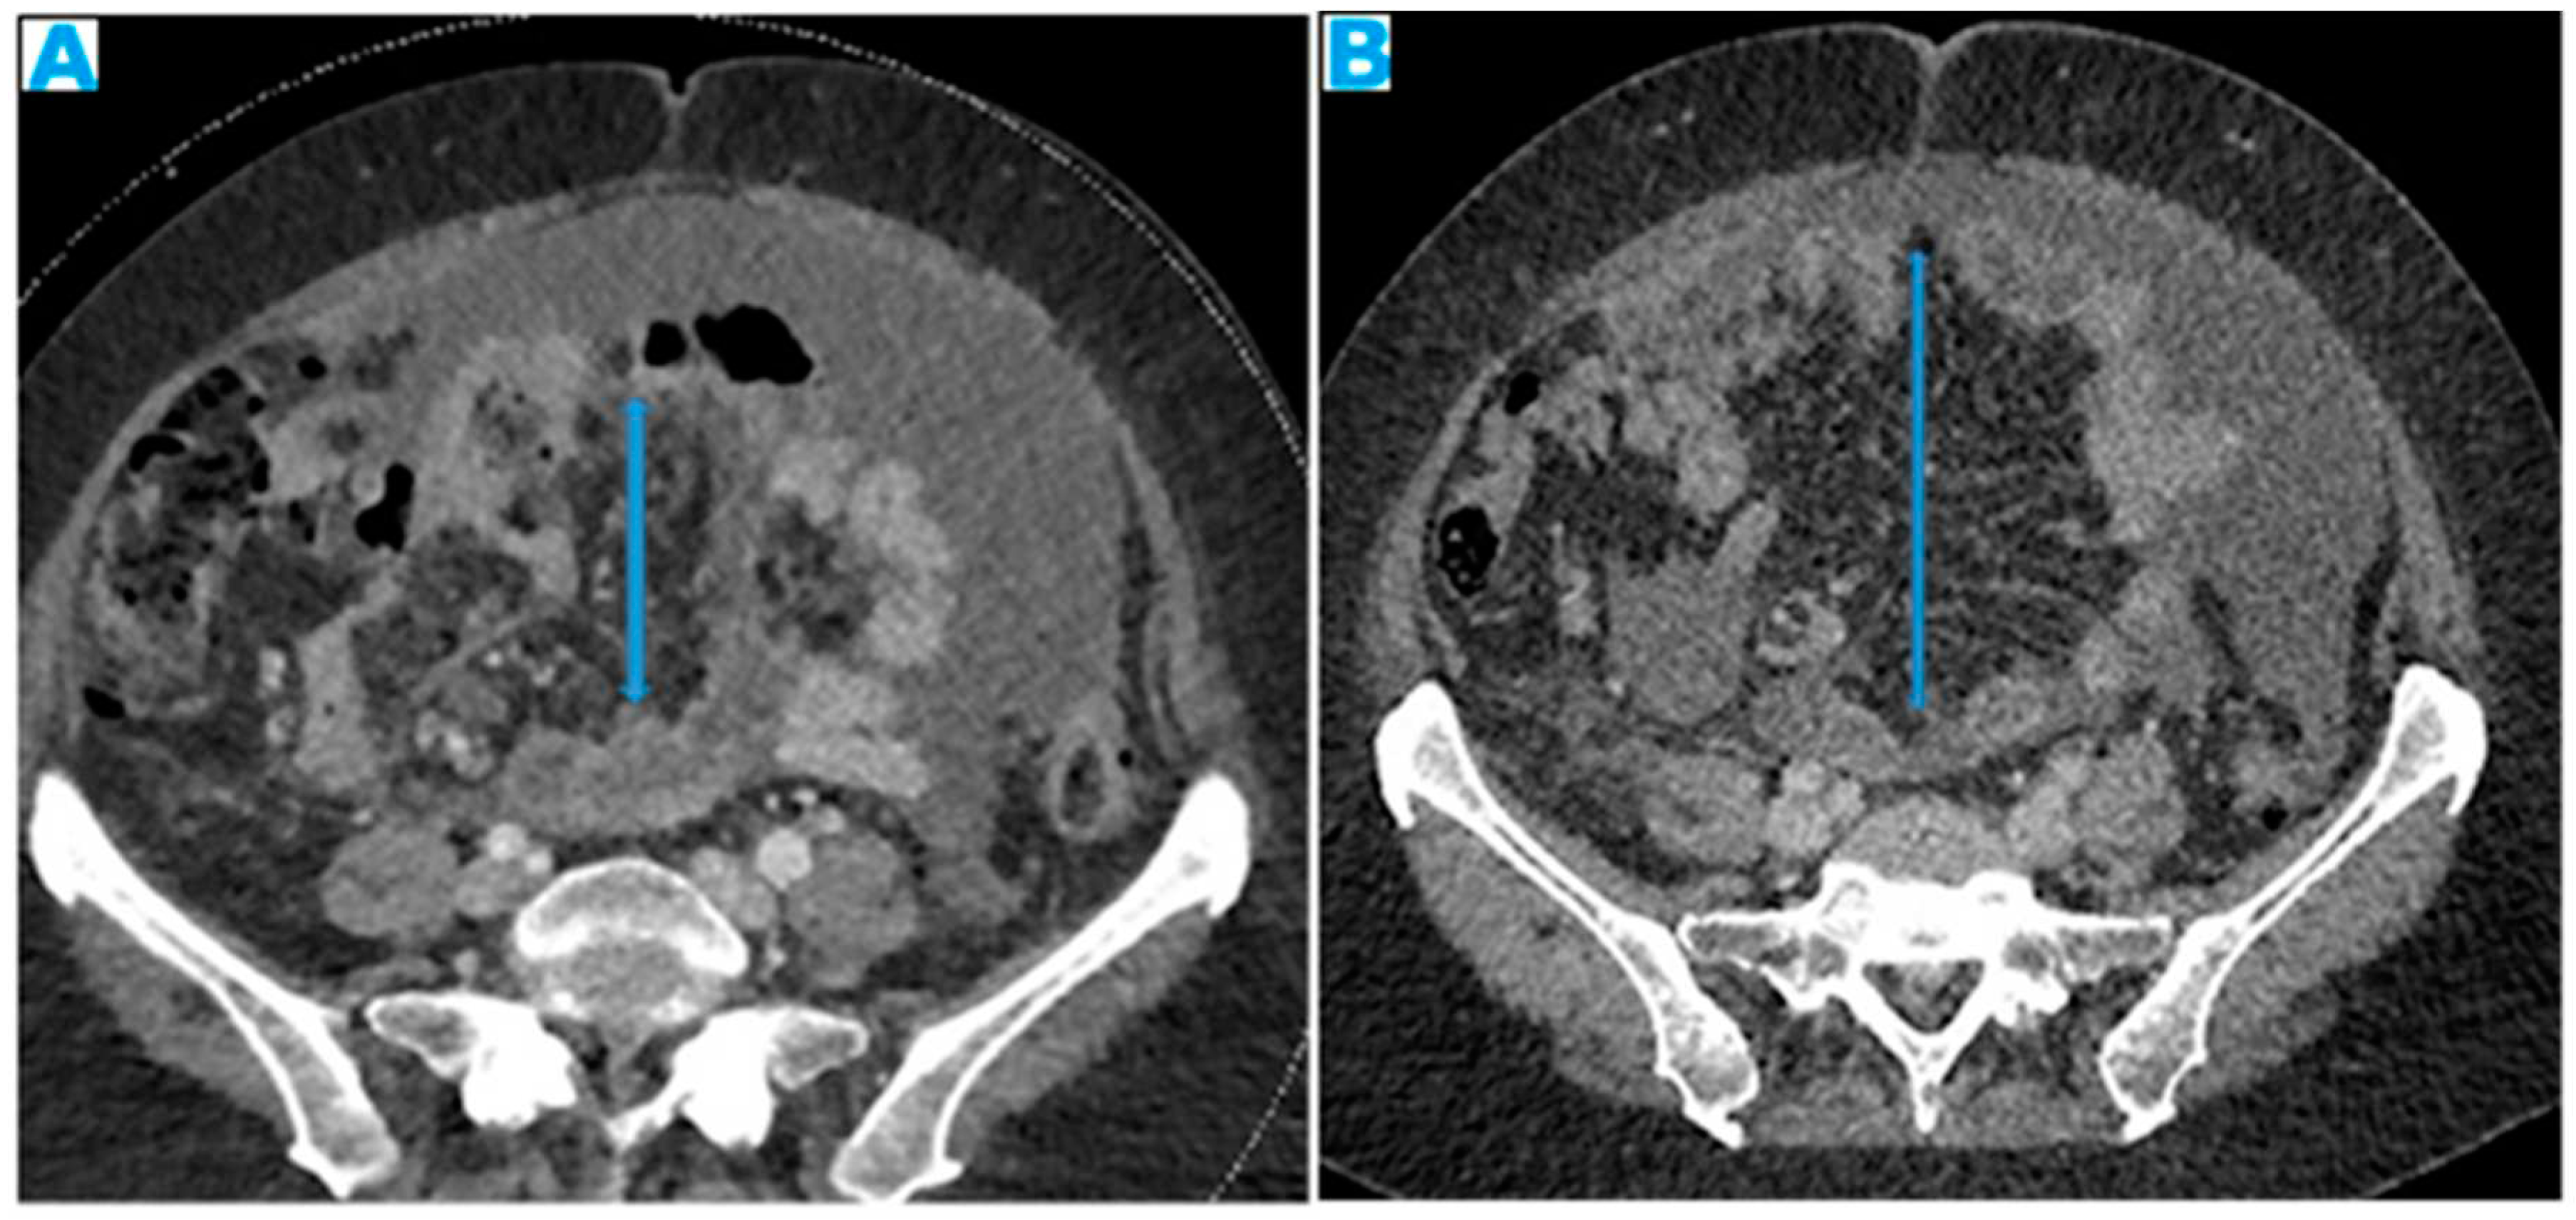

Figure 27.

Axial T2WI (A). PC from mucinous adenocarcinoma of the uracus: Notice the hyperintense mesenteric deposits (*) (signal due to mucin content) and how the SB loops appear separated and angulated (arrow). Axial T2WI (B), axial CE portal phase FST1WI (C). PC from breast carcinoma: Mesenteric deposits (arrowheads on B) make SB loops appear thickened and separated. Notice how deposits are more conspicuous on T2WI due to its high tissue contrast. Axial CE-CT (D). PC from ovarian carcinoma: Clustered small bowel loops as the end point of mesenteric seeding.